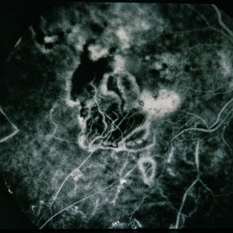

BRVO - Massive Exudate from Collaterals

Feb 24 2014 by David Callanan, MD

66-year-old female with BRVO - massive exudate from collaterals, 20/70 OD; 20/25 OS in 1985; +HTN, glaucoma; 20/200 OD 1987.

Condition/keywords: branch retinal vein occlusion (BRVO), collaterals, exudate